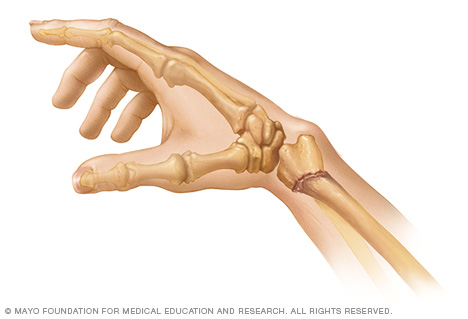

Cuánto tiempo dura la rehabilitacion de. El extremo inferior del hueso se rompe bastante cerca del lugar donde se conecta con los huesos que pertenecen a la mano al lado del pulgar de la muñeca. Una quebradura de muñeca es una fractura o fisura en uno o más huesos de la muñeca.

Una fractura ocurre cuando hay una rotura o fisura en uno o más de los huesos. Este tipo de fractura se puede producir de muchas maneras diferentes. Las lesiones más frecuentes se producen en la muñeca cuando las personas intentan sujetarse durante una caída y cuando caen al suelo con la mano extendida.